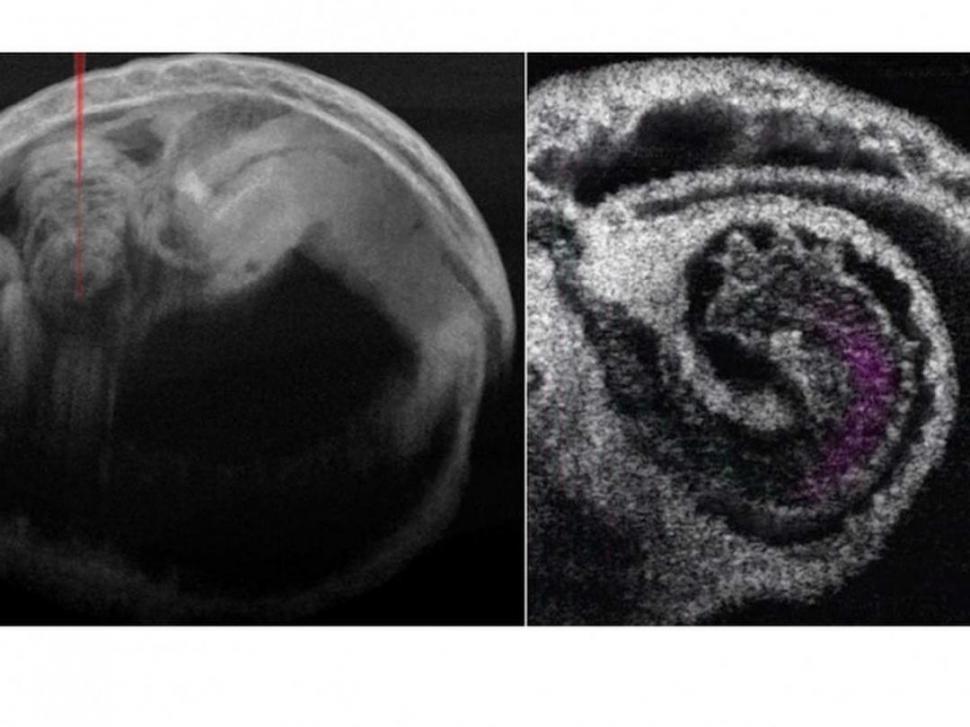

El estudio demuestra la riqueza de los datos proporcionados por este enfoque y su viabilidad para investigar la relación funcional entre el flujo sanguíneo y la dinámica de la pared del corazón dentro de diferentes regiones del corazón embrionario de mamífero, una posibilidad a la que no se puede acceder actualmente por otros métodos. El enfoque puede utilizarse potencialmente para evaluar el bombeo cardíaco sobre el desarrollo embrionario a medida que se remodela el tubo cardíaco, lo que podría revelar cambios funcionales durante la cardiogénesis temprana.

“El innovador método ofrece una nueva forma de estudiar la biomecánica del desarrollo cardíaco. El análisis de las imágenes de TCO 4D permitió relacionar el flujo sanguíneo, la resistencia al flujo y los gradientes de presión inducidos por los movimientos de la pared del corazón”, comenta Amy L. Oldenburg, de la Universidad de Carolina del Norte (EEUU).

Aunque tradicionalmente se ha pensado que el mecanismo que bombea la sangre dentro del tubo cardíaco embrionario son las contracciones peristálticas ondulantes, los investigadores pudieron ofrecer una evaluación más detallada utilizando la TCO 4D. Sus observaciones piloto sugieren que el bombeo localizado del tubo cardíaco en los ventrículos funciona a través de una combinación de mecanismos de succión y empuje.